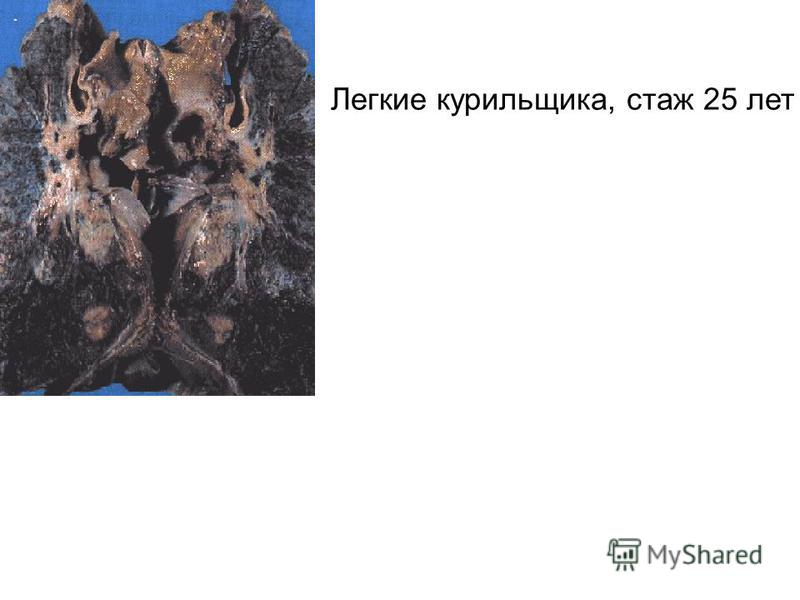

Здоровый образ жизни: Влияние курения